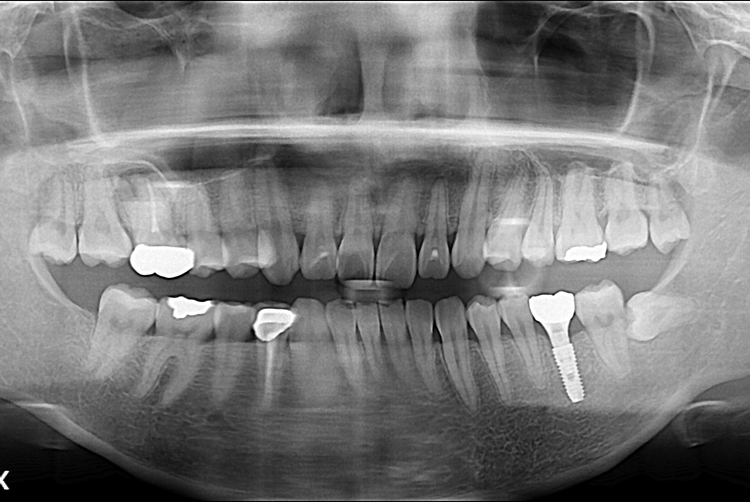

[임플란트] 어금니 임플란트

치료전 : 2019-04-11